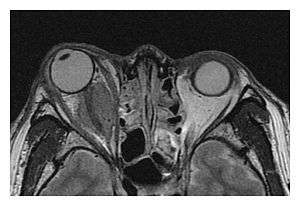

| Mass lesion around the right optic disc in a 44-year-old man with IgG4-related ophthalmic disease and a serum IgG4 of 599 mg/dL.[1] (T2-weighted MRI) | |

IgG4-related ophthalmic disease (IgG4-ROD) is the recommended term to describe orbital (eye socket) manifestations of the systemic condition IgG4-related disease,[2] which is characterised by infiltration of lymphocytes and plasma cells and subsequent fibrosis in involved structures. It can involve one or more of the orbital structures.

The extent of inflammation that can occur in IgG4-ROD is well demonstrated on magnetic resonance imaging (MRI).